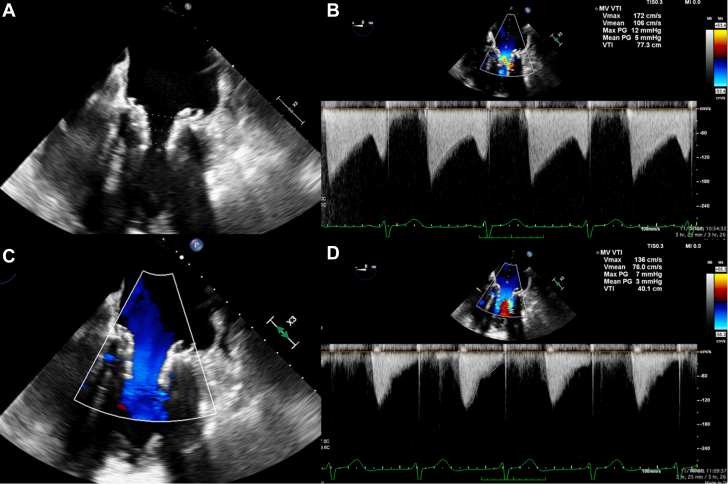

Figure 4.

Intraprocedural Transesophageal Echocardiography Imaging

(A and B) After valve deployment, underexpansion of the valve frame resulted in tapering of the inner frame from 17.2 mm (atrial) to 9.7 mm (ventricular). The peak and mean mitral valve (MV) gradients were 12 and 5 mm Hg, respectively. (C and D) Following postdilation, there was improved frame expansion, with a final mean MV gradient of 3 mm Hg. PG = pressure gradient; VTI = velocity time integral.

Postimplant TEE demonstrated excellent bioprosthetic valve function without central or paravalvular leak, and a mean mitral valve gradient of 3 mm Hg (Figure 4). There was no significant left ventricular outflow tract obstruction. A 5.1-mm atrial septal defect with left-to-right shunting remained.